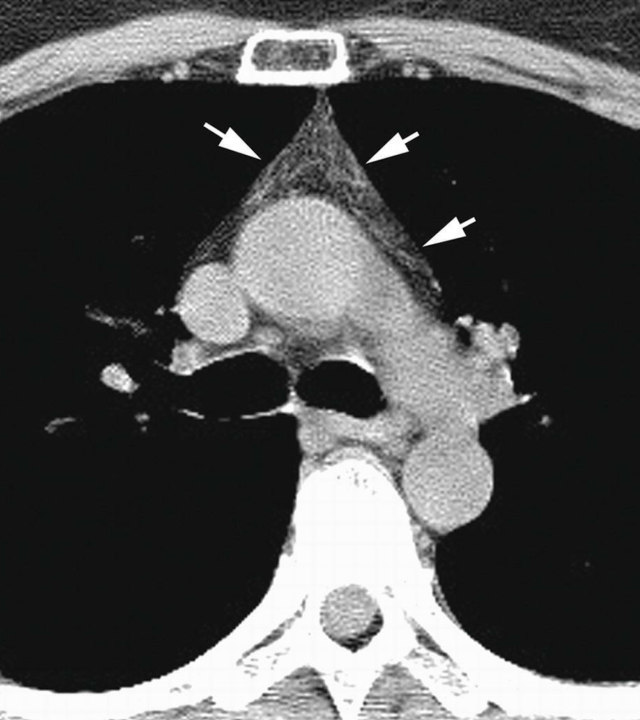

常见的正常胸腺及胸腺病变的ct表现 吕晓飞.ppt

图片尺寸1152x864